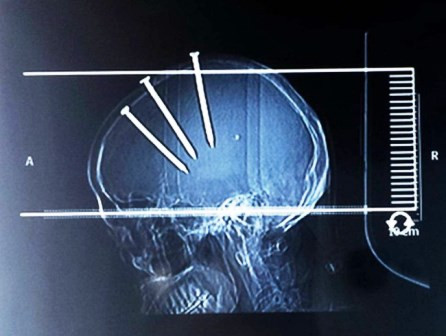

Hình ảnh chụp X-Quang cho thấy những chiếc đinh dài đâm xuyên qua đầu của người đàn ông đi thẳng vào não. Mặc dù vậy, người đàn ông này đã qua cơn nguy kịch sau khi được tiến hành phẫu thuật lấy những chiếc đinh ra.